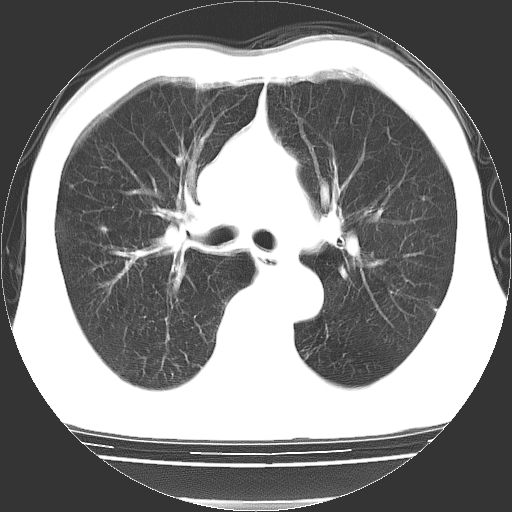

以下是引用hhcckk在2009-1-1 15:38:00的发言:[br]左下肺少许絮状模糊影--考虑感染[br]两肺散在小点状密度增高影--结合病史考虑矽肺?[br]气管壁钙化--可能由于老年退变性引起的